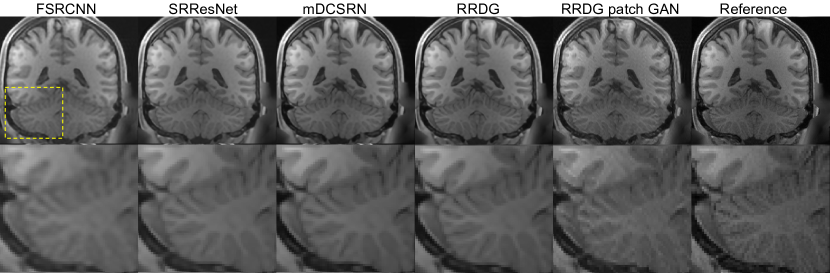

Refer to caption

Figure 4: Left to right: Super-resolution output from FSRCNN, SRResNet, mDCSRN, RRDB, RRDB with patch GAN training, and ground truth. Bottom row is magnified portion of the same image region across the different SISR outputs.

Our proposed RRDG and its patch GAN augmented variant were evaluated against state-of-the-art FSRCNN, SRResNet, and mDCSRN models for SISR reconstruction. The FSRCNN and SRResNet are adapted to 3D directly. For the mDCSRN, we used the b8u4 configuration, 8 dense blocks with 4 dense layers within each block. Example results are illustrated in Fig. 4. Visually the output from RRDB is most sharp and the GAN oriented model successfully recover qualitatively more realistic brain image texture.